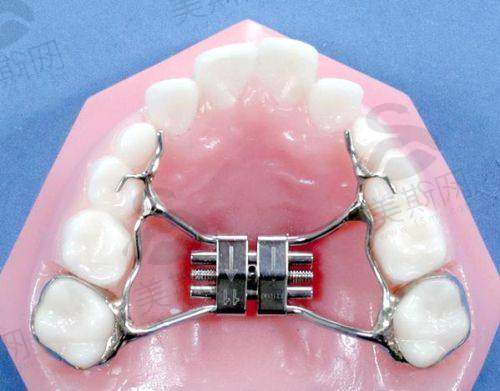

2. 牙齿矫正:提供传统金属托槽、自锁托槽、陶瓷半隐形、隐形矫正等多种方案,引进美国隐适美、时代天使等有名隐形矫正版牌,通过3D口扫技术提前预知矫正成效,满足不同年龄层患者的美观需求。

另一项特色技术是隐形矫正数字化方案设计,采用美国隐适美iTero口内扫描仪,3分钟即可完成口腔数据采集,即时生成3D矫正动画,患者可直观看到矫正过程和更终成效。医生根据动画方案调整矫正步骤,定制一系列透明矫治器,患者每天佩戴22小时,每2周更换一副,定期复诊微调,全程无钢丝托槽,不影响美观和日常生活。该技术适用于牙列拥挤、牙缝过大、龅牙、地包天等多种错颌畸形,矫正周期比传统托槽缩短1/3,且复诊次数少,深受年轻患者青睐。